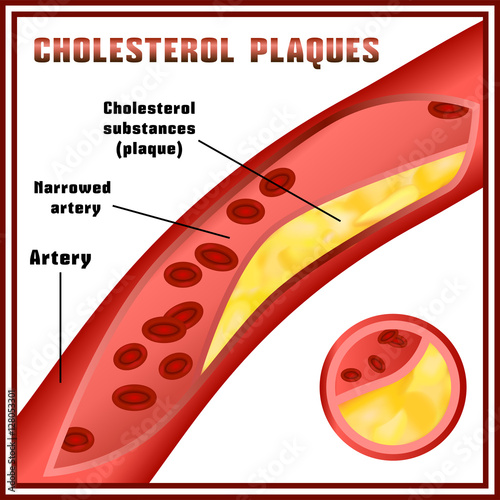

Cholesterol plaque in artery – Vida Abuelo

Pin on Cholesterol & Blocked Arteries

Arterial plaque | Serrapeptase

Foods That Dissolve Artery Plaque